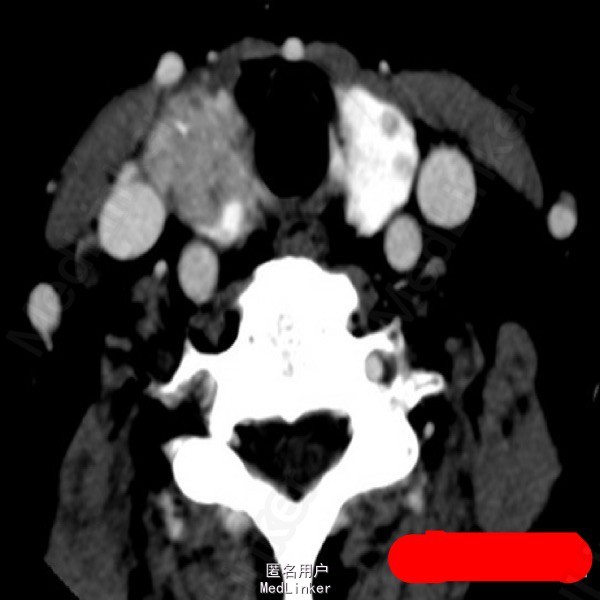

甲状腺癌

中年女性,发现颈部肿物半年,轻度吞咽困难1月。超声提示颈部可见甲状腺低回声结节,内见点状强回声。术后病理:甲状腺乳头状癌。问题:想问问大家对于甲状腺癌术后碘131治疗怎么看?